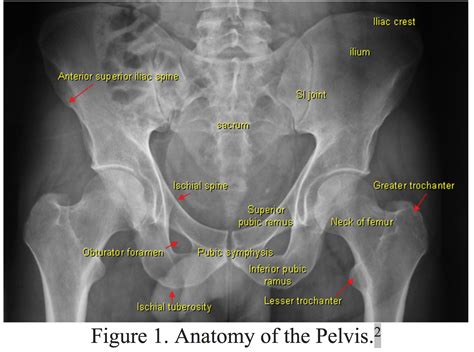

Anatomy of the Inferior Pubic Ramus

The inferior pubic ramus is a part of the pubis bone, which is one of the three bones that make up the pelvis. The pubis bone is located in the anterior (front) part of the pelvis and is connected to the ischium and ilium bones. The inferior pubic ramus extends downward and medially from the pubic symphysis, the cartilaginous joint that connects the two pubic bones.

The inferior pubic ramus is a thin, flat bone that forms the lower border of the obturator foramen, a large opening in the pelvis. This foramen is bounded by the pubis and ischium bones and serves as a passage for several important structures, including nerves and blood vessels.